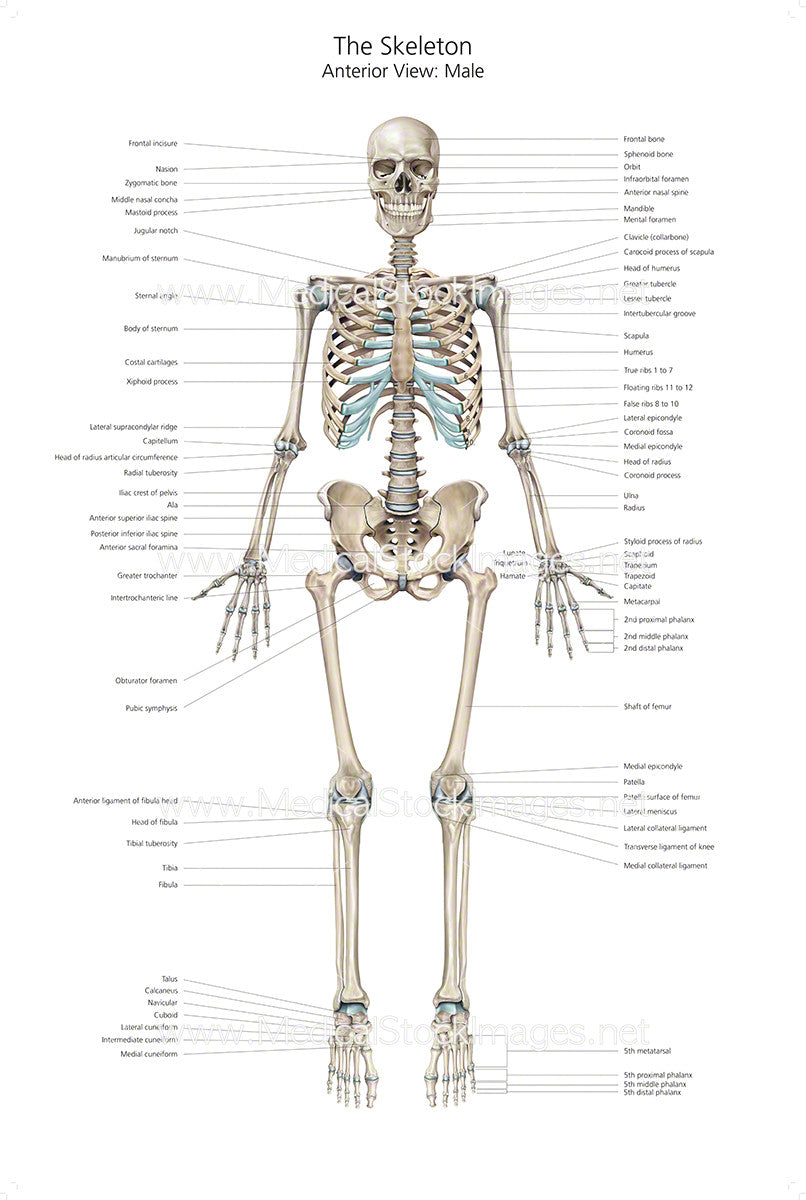

anterior view of human skeleton Skeleton front

Femur Labeled Anterior View

diagramdataplantings.z21.web.core.windows.netAnterior Skeletal System

diagramdataplantings.z21.web.core.windows.netAnterior Skeletal System

![Free download wallpapers Skeleton Wallpapers [1600x1200] for your](https://img.wallpapersafari.com/desktop/1600/900/71/38/d3ibyr.jpg) wallpapersafari.comAnterior View Of Human Skeletal System, With Labels Stock Photo - Alamy

wallpapersafari.comAnterior View Of Human Skeletal System, With Labels Stock Photo - Alamy

www.alamy.comanterior skeletal system human labels alamy

www.alamy.comanterior skeletal system human labels alamy

animalia-life.clubMale Human Skeleton Front View Stock Illustration 149433725 | Shutterstock

animalia-life.clubMale Human Skeleton Front View Stock Illustration 149433725 | Shutterstock

Human Skeleton Diagram Anterior View On Stock Photo 322625621